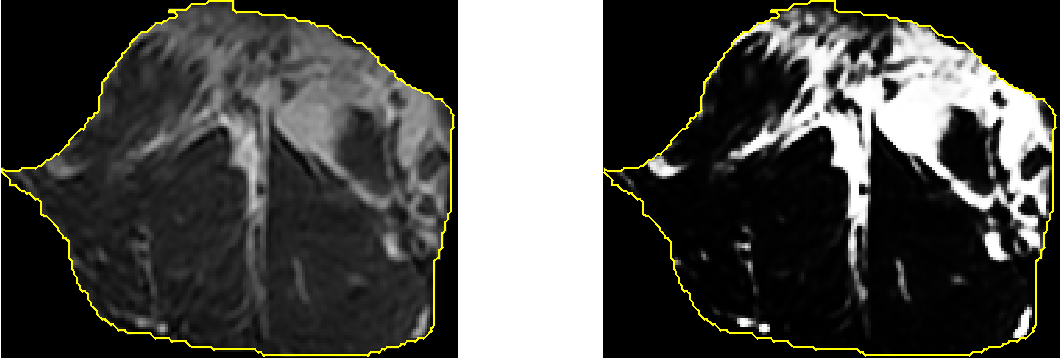

Every pixel p(x,y)𝑝𝑥𝑦p(x,y) in the segmented lumbar muscle region is subjected to the sigmoid function s(x,c,a)𝑠𝑥𝑐𝑎s(x,c,a) which gives a clear discrimination between the muscle region and the fatty region pfat(x,y)subscript𝑝𝑓𝑎𝑡𝑥𝑦p_{fat}(x,y) as shown in Fig. 4.

Refer to caption

Figure 4: Detected fatty region from the segmented muscle region (with threshold 80 and softness 0.1)

In the sigmoid function, choosing different values for the centre c𝑐c is associated with the threshold selection for discerning the fatty region from the muscle region. Similarly varying the values of slope control a𝑎a in the sigmoid function is associated with the softness level of the discerned fatty region edges. Pixel p(x,y)𝑝𝑥𝑦p(x,y) belongs to “fat”, if the pixel intensity is above the threshold selected by adjusting the centre c𝑐c value in the sigmoid function s(x,c,a)𝑠𝑥𝑐𝑎s(x,c,a).

For example, considering the segmented region shown in Figure 4, the total pixels in the segmented lumbar muscle region were 21,156 and the pixels in the fatty region were 3,733 and the computed total fat content was 17.6 %.